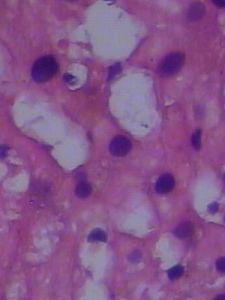

臨床診斷疾病往往有一定的偏差,只有病理診斷才確實可靠。有時臨床診斷是急性肝炎,而病理則提示為慢性肝炎的急性發作;臨床診斷是急性或亞急性重型肝炎,而病理提示為在肝硬變的基礎上發生的大塊或亞大塊壞死,即慢性重型肝炎;臨床上診斷慢性肝炎或病毒攜帶者,而病理提示為早期肝硬化等等。還有一些非病毒性肝炎肝損害的患者,單憑血化驗、B超、CT等檢查很難與病毒性肝炎鑑別。例如,張鴻飛曾對1020例小兒肝活檢進行分析,顯示非病毒性肝損害占9.6%(98例),其中病因達18種之多,前五位是:a.與脂類代謝有關的疾病;b.肝豆狀核變性;c.肝糖原儲積症;d.進行性肌營養不良;e.自身免疫性肝炎。由此,肝活檢可以為肝病的診斷提供重要的線索。

慢性病毒性肝炎者肝臟的炎症和纖維化程度與治療及預後有密切的關係,只有臨床症狀和化驗結果,沒有肝活檢很難作出正確的判斷。例如B肝病毒攜帶者,經肝穿肝組織活檢發現10%的人肝組織基本正常;70%的人肝組織有輕微的病變;20%的人有慢性活動性肝炎,肝硬化。前80%的人可不需治療,後20%的人則一定要治療。還有重型肝炎的嚴重性與肝細胞壞死的程度有直接的關係。計算肝活檢組織內肝細胞體積的比例,可估計重型肝炎的預後。凡肝細胞體積的比例<10%者全部死亡,>35%者則恢復意識。有人對22例重型肝炎作了多次肝活檢,發現意識恢復的病人,肝細胞再生後肝組織內肝細胞體積的比例>45%。在重型肝炎病人的恢復過程中,複查肝活檢,根據肝細胞恢復程度和纖維組織增生程度,對預後也有一定的參考意義。病理顯示肝細胞破壞嚴重,肝小葉結構紊亂,纖維組織增生多,預示病人將發展到肝硬變。